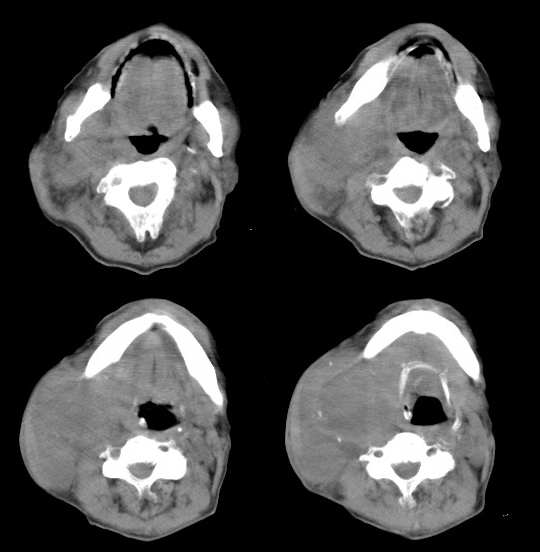

右颈部巨大软组织肿块影,范围较广,上至下颌角,下至颈静脉切迹。其最大层面位于右侧甲状腺区。肿块密度不均,其中有坏死液化区和班片状钙影,增强扫描见肿块实质区有强化。邻近结构挤压移位,部分结构侵蚀破坏,右侧多个颈深淋巴结肿大。两肺弥漫分布小结节影,以胸膜下为主,其大小不等,边缘光整。右侧胸壁亦见软组织结节影,纵隔多个淋巴结肿大及两侧锁骨上淋巴结肿大。

意见:右侧甲状腺癌并两肺、胸壁、纵隔淋巴结、颈深淋巴结、锁骨上淋巴结等广泛转移。